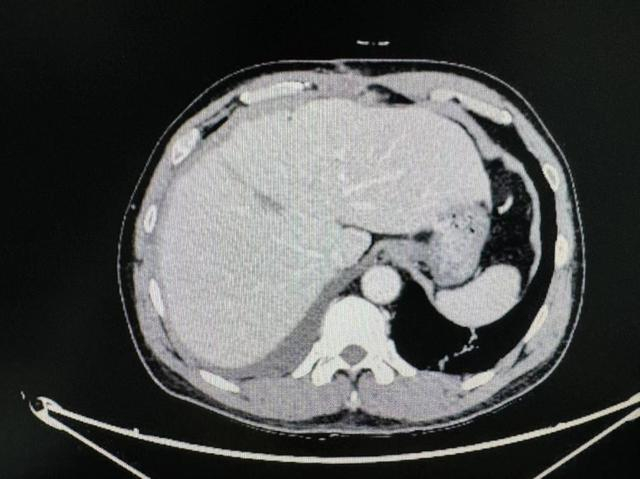

在住院期间,患者查上腹部CT后提示肝左右叶交界处肝癌,经同济医院肝胆外科中心主任谭蔚锋会诊后进行后续治疗。

术前影像学资料

1月4日行腹腔镜下特殊肝段切除术(肝中叶IVA+VIII段),术中病理为肝细胞癌。